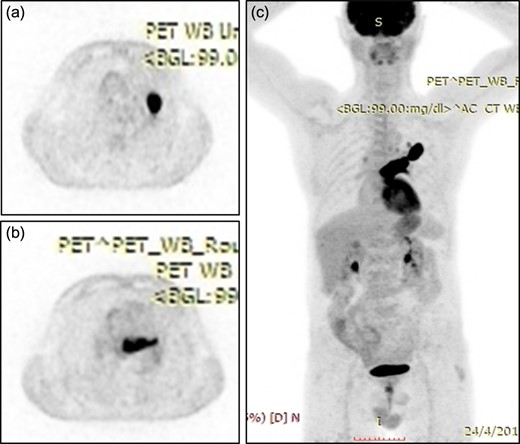

A 61-year-old male, with a history of heavy tobacco abuse presented with dyspnea, left thoracic pain and productive cough. He did not report palpitations or hemoptysis. Chest radiography showed an abnormal shadow in the left upper lung field. Computed tomography (CT) scan revealed a solid lesion of the left upper lobe, 2.9 × 1.8 cm2 in size, with irregular borders (Fig. 1a and c). The tumor seemed to infiltrate the upper left pulmonary vein which appeared dilated and totally occluded due to the presence of thrombotic material in its lumen (Fig. 1b and d). Transthoracic echocardiography showed an intracardiac structure, 4 × 2.5 cm2 in size, protruding from the left pulmonary vein, having no adhesions to the atrial walls. Magnetic resonance imaging (MRI) confirmed the above findings. (Fig 2a–d). A positron emission tomography scan (PET) was also performed. It confirmed the CT findings showing an irregular nodular lesion in the left upper lobe with irregular margins and a diameter of 2.8 cm. It showed a hypermetabolic activity (SUVmax = 29.6) (Fig. 3a and c). It also showed a pleural lesion ventrally to the upper lobe parenchyma. Another hypermetabolic focus (SUVmax = 21.4) appeared in the lumen of the upper lobe pulmonary vein (Fig. 3b and c). Bronchoscopy showed the presence of abnormal tissue in the apicoposterior segmental bronchus of the left upper lobe. Tissue biopsies were obtained but showed no signs of malignancy. Spirometry revealed a mild obstructive pattern. A complete staging work-up, including head CT scan, abdominal ultrasound and whole body bone scintigraphy, did not show any distant metastasis. Based on these the preoperative staging was T4N0M0. Despite failure to obtain a pathologic diagnosis, a surgical treatment including left pneumonectomy with entry in the left atrium and removal of the intracardiac thrombus under cardiopulmonary bypass (CPB) was decided based on the potential immediate life-threatening situation. The presence of such an intracardiac thrombus could be associated with secondary migration, acute blockage of the mitral valve and heart failure, or a distal arterial embolisation resulting into a fatal stroke, a mesenteric ischemia or a severe peripheral ischemia [2, 4]. Median sternotomy was the surgical approach and the patient was cannulated using bicaval venous return and underwent CPB. Left pneumonectomy was carried out, initially with left pulmonary artery ligation and resection, followed by resection of the left pulmonary veins and part of the wall of the left atrium together with the intraatrial mass, which was removed en bloc. The left atrium was sutured closed and then the left main bronchus was resected, completing the left pneumonectomy. The nodal stations 4, 5, 7, 8 and 9 were also sampled. The surgical specimen (Fig. 4) showed the same features as those seen on the CT scan. The patient was successfully extubated directly after the operation and was transferred to the ward on the first postoperative day. The patient was discharged on the 12th postoperative day and received adjuvant chemotherapy thereafter.

(a) Positron emission tomography scan showing an irregular nodular lesion in the left upper lobe with irregular margins and hypermetabolic activity. (b) Hypermetabolic focus in the lumen of the upper lobe pulmonary vein. (c) Coronar reconstruction showing the focal hypermetabolic activity in the left upper lobe, the left atrium and the left upper pulmonary vein.